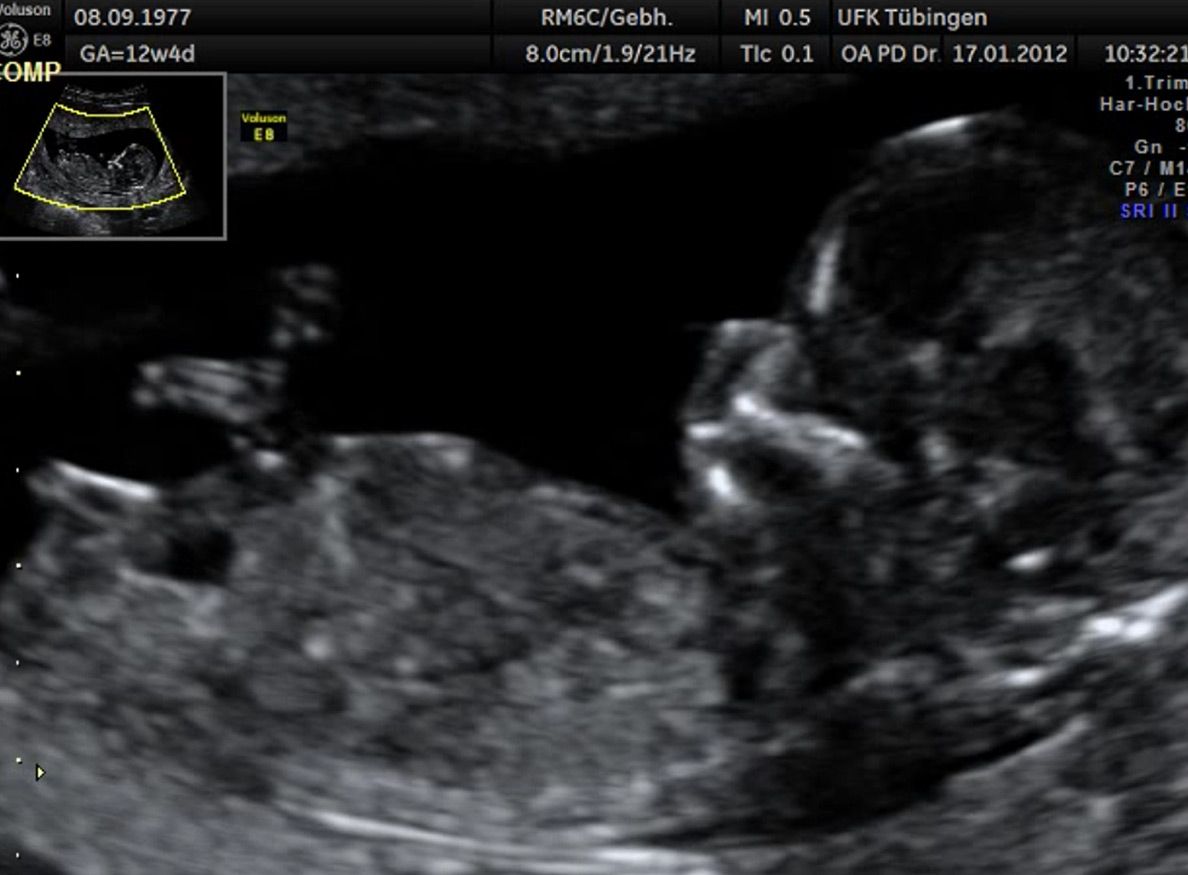

Bauchwanddefekt

Obwohl der Fet zu diesem Zeitpunkt erst zwischen 5 und 8cm groß ist, lassen sich bereits etwa die Hälfte aller schwerwiegenden Fehlbildungen erkennen bzw. ausschließen. Sollten wir eine Auffälligkeit sehen, werden wir mit Ihnen den Befund und das weitere Vorgehen ausführlich besprechen.

Es sollte berücksichtigt werden, dass strukturelle/anatomische Fehlbildungen (z.B. angeborene Herzfehler) deutlich häufiger auftreten. Bei etwa 2-3% (1:30 - 1:50) der Feten werden Fehlbildungen gefunden. Diese können isoliert, d.h. ohne Chromosomenstörung auftreten. Sie werden aber gehäuft bei Trisomien und andersartigen Veränderung des Erbguts gefunden. Daher ist eine detaillierte Ultraschalluntersuchung im Rahmen der Risikobeurteilung unerlässlich. Sollte eine Fehlbildung erkannt werden, so ist eine Risikoberechnung für Trisomie 21 alleine nicht ausreichend. Hier sollte eher an eine Fruchtwasser- oder Mutterkuchenpunktion gedacht werden, um eine Chromosomenstörung erkennen oder ausschließen zu können.